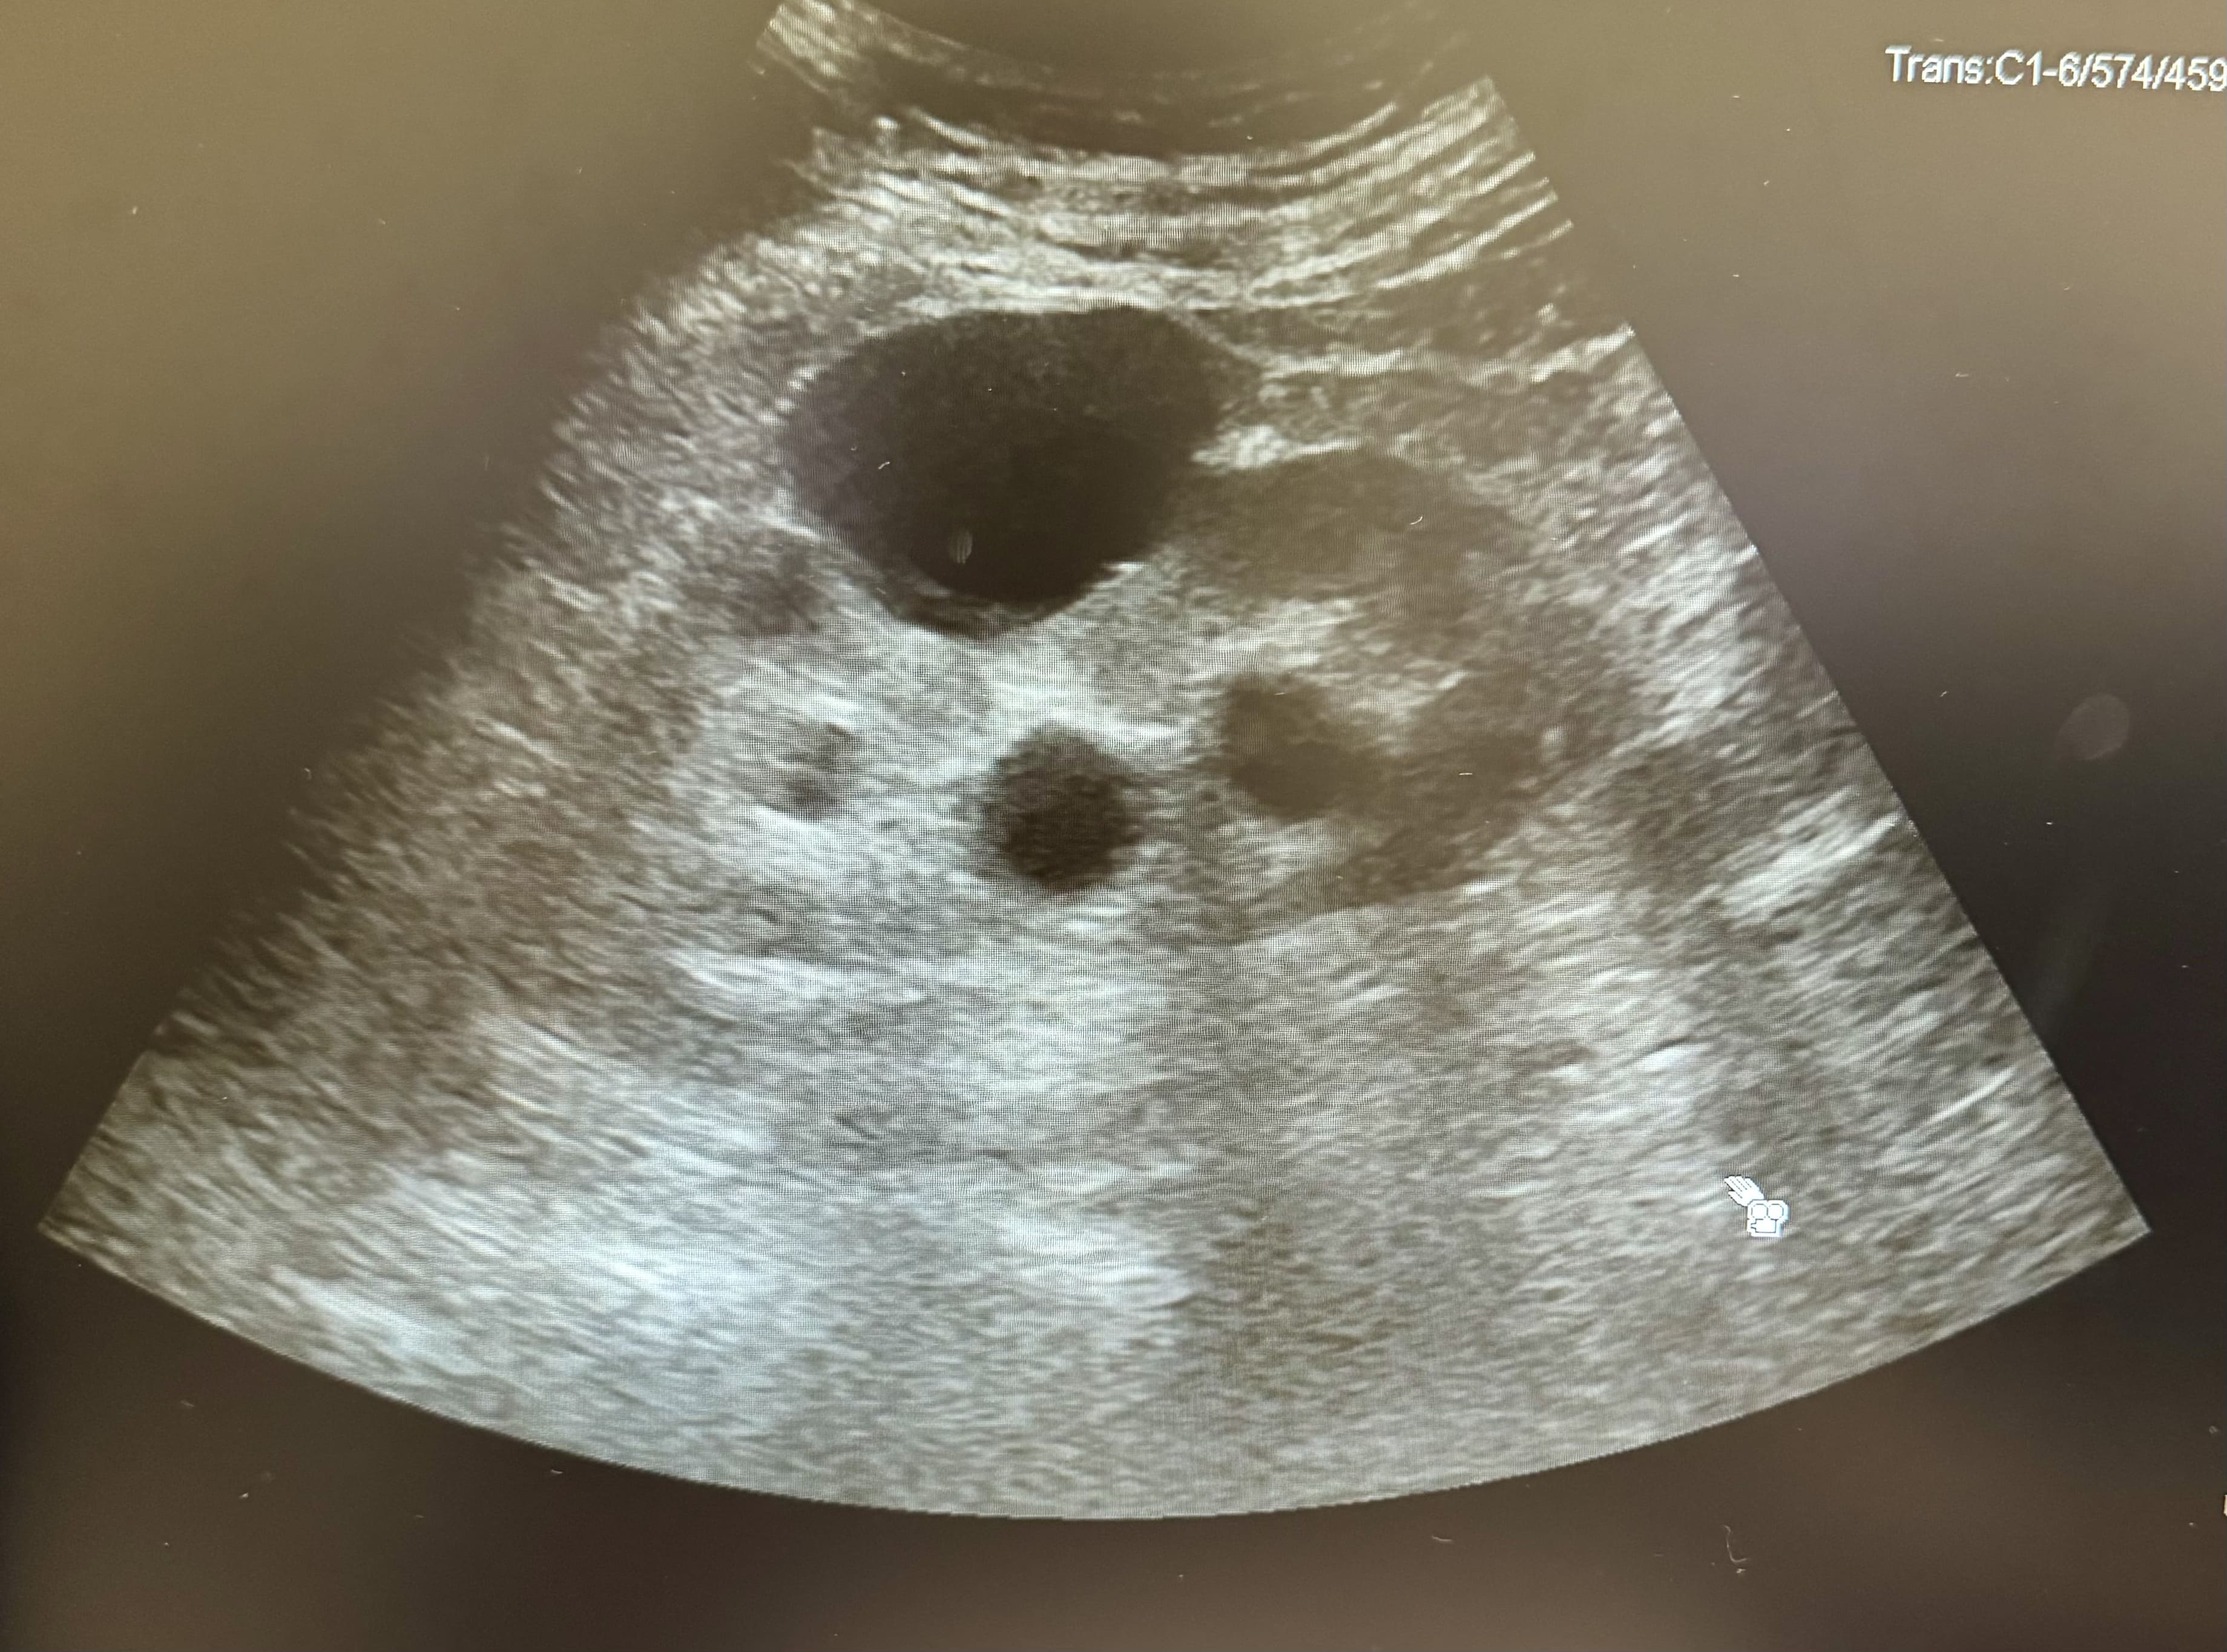

Hombre de de 73 años que acude a consulta de urgencias por dolor en fosa renal derecha desde hace 2 semanas irradiado hacia hemiabdomen derecho. En ese contexto pérdida de control de esfínter con escapes de orina especialmente nocturnos. Refiere además desde hace dos meses dificultad para el inicio de la micción, polaquiuria y nicturia asociadas sin disuria. Sin fiebre ni sensación distérmica en domicilio. No otra clínica por sistemas o aparatos.

La ecografía POCUS es una herramienta de gran valor en situaciones de emergencia y en el ámbito de la medicina de familia. Su uso permite un diagnóstico rápido de la retención urinaria, la evaluación del estado renal (hidronefrosis) y la identificación de la causa subyacente (hipertrofia prostática). Además, facilita intervenciones inmediatas y permite el seguimiento continuo en pacientes con enfermedades crónicas del tracto urinario.